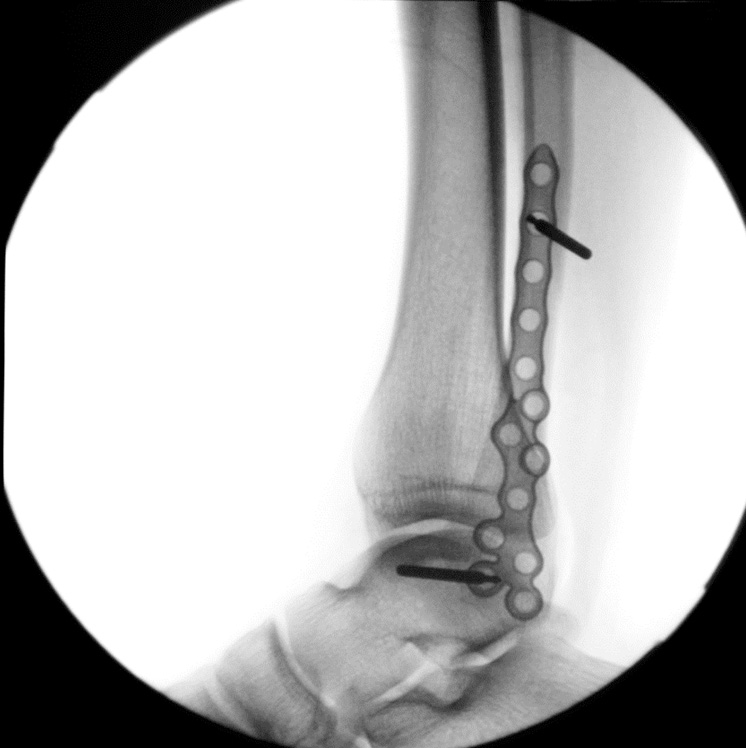

Ortholucent implants from GLW Medical deliver a true evolution in orthopedic fixation. Traditional metal implants block X‑rays and distort CT/MRI imaging, but GLW Medical’s hybrid titanium–composite devices are strong, visible, and imaging‑translucent—allowing surgeons to see both implant and bone with unprecedented clarity. This potentially enhances surgical precision, accelerates clinical decisions, and supports faster patient recovery, while enabling a scalable platform spanning screws, nails, plates and MIS guides, as well as single‑use instruments.

Allows for better visualization of bones and joints on X-rays and other imaging techniques, which can help surgeons assess fracture reduction and post-operative healing.

The lower titanium load which is reinforced by PEEK (polyetheretherketone) provides clear bone visibility during plain radiography as well as less scatter with advanced imaging techniques. Improved visualization enables the clinician to interpret bone healing with greater confidence leading to faster advancement of recovery protocols.

Patented Technology

GLW Medical’s MIS portfolio introduces reproducible, patent‑pending radiolucent guides paired with its patented ortholucent implants. These solutions feature single‑use, disposable radiolucent targeting guides and specialized instrumentation built for minimally invasive foot and ankle procedures. The radiolucent construction improves visualization on X-rays during MIS, while internal alignment features enhance accuracy, consistency, and workflow efficiency in procedures where exposure is inherently limited.

Together, MIS techniques and imaging‑translucent implants form a powerful competitive advantage: MIS increases the need for clear, reliable imaging, while ortholucency directly enhances MIS accuracy and confidence. Both elements are protected by a unified, difficult‑to‑replicate patent estate that scales across multiple orthopedic categories.